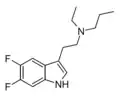

Substituted tryptamines, or serotonin analogues, are organic compounds which may be thought of as being derived from tryptamine itself. The molecular structures of all tryptamines contain an indole ring, joined to an amino (NH2) group via an ethyl (−CH2–CH2−) sidechain. In substituted tryptamines, the indole ring, sidechain, and/or amino group are modified by substituting another group for one of the hydrogen (H) atoms.

| Chemical structure | Short Name | Origin | Ring Substitution | RN1 | RN2 | Full Name | CAS Number |

|---|---|---|---|---|---|---|---|